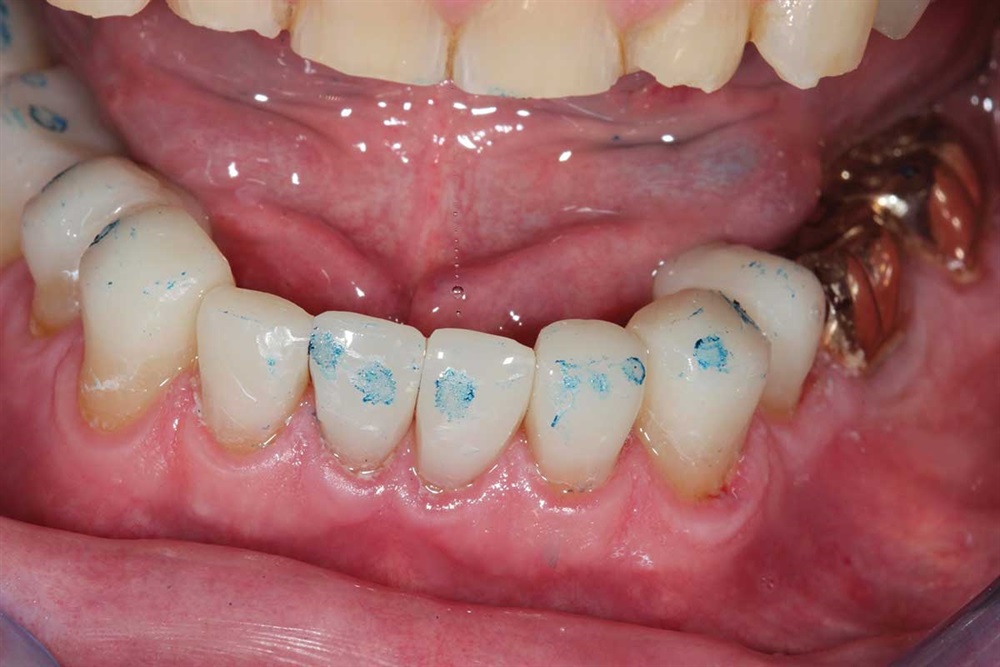

Fig. 40: Plaque.

Show Your Work

Fig. 41: Occlusion being adjusted. I did not increase his vertical when I did the upper teeth.

Fig. 42: Marks show heavier contact in lateral and protrusive excursions. Again, light occlusion on the centrals because of the lack of support I was bonding to.